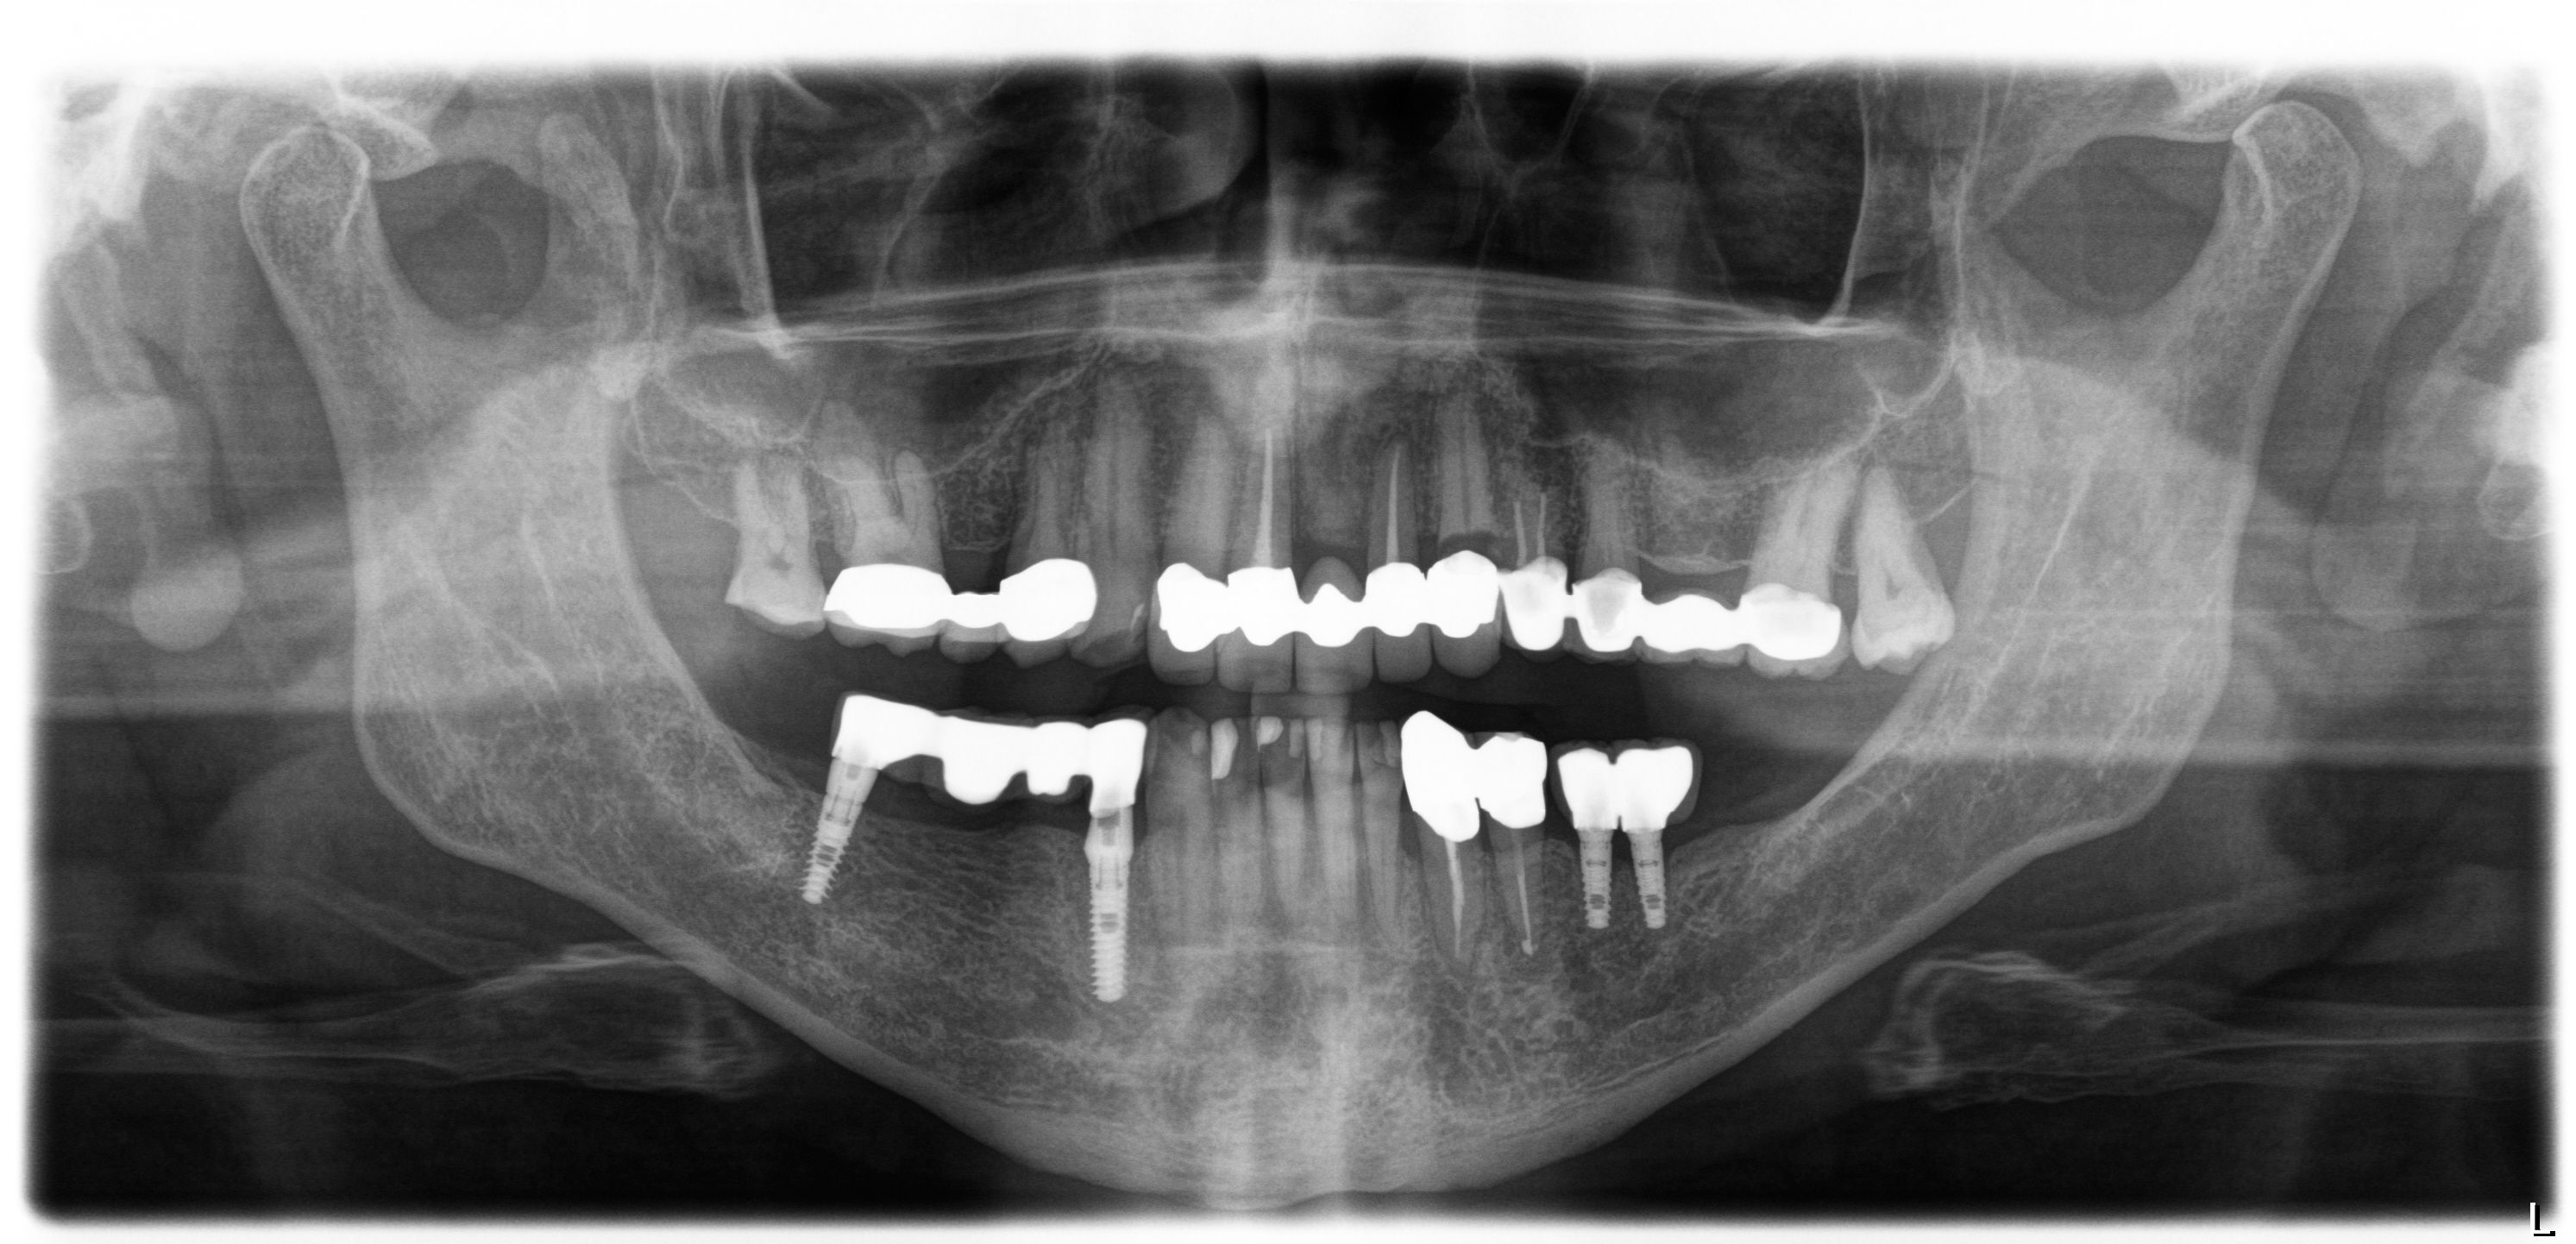

Implantat setzen und Kronenversorgungen

I. Befund des gesamten Gebisses / Behandlungsplan

Oberkiefer

Unterkiefer

Bemerkungen (bei Wiederherstellung Art der Leistung)

• mit Freilegung

• mit Auswechseln der Sekundärteile

• Knochenaufbau: 1x Regio 23

• Computertomografie